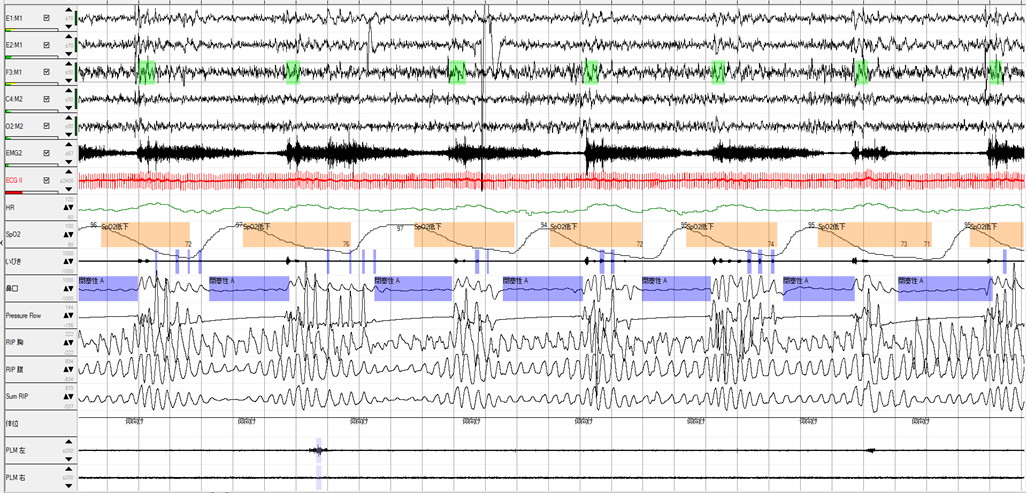

高度な酸素飽和度低下を示した閉塞性無呼吸波形です。呼吸イベントの持続時間が23秒でも、酸素飽和度は71%まで低下しています。高度肥満例ならあり得るのですが、この症例のBMIは27でしたので、軽度肥満例でした。なぜこのような高度な酸素飽和度低下を示したのか、それは無呼吸だけでなく、低換気の病態が重畳しているのではないかと考えました。実はPSG開始前に飲酒もされており、服薬+アルコールによって生じた低換気と思われます。